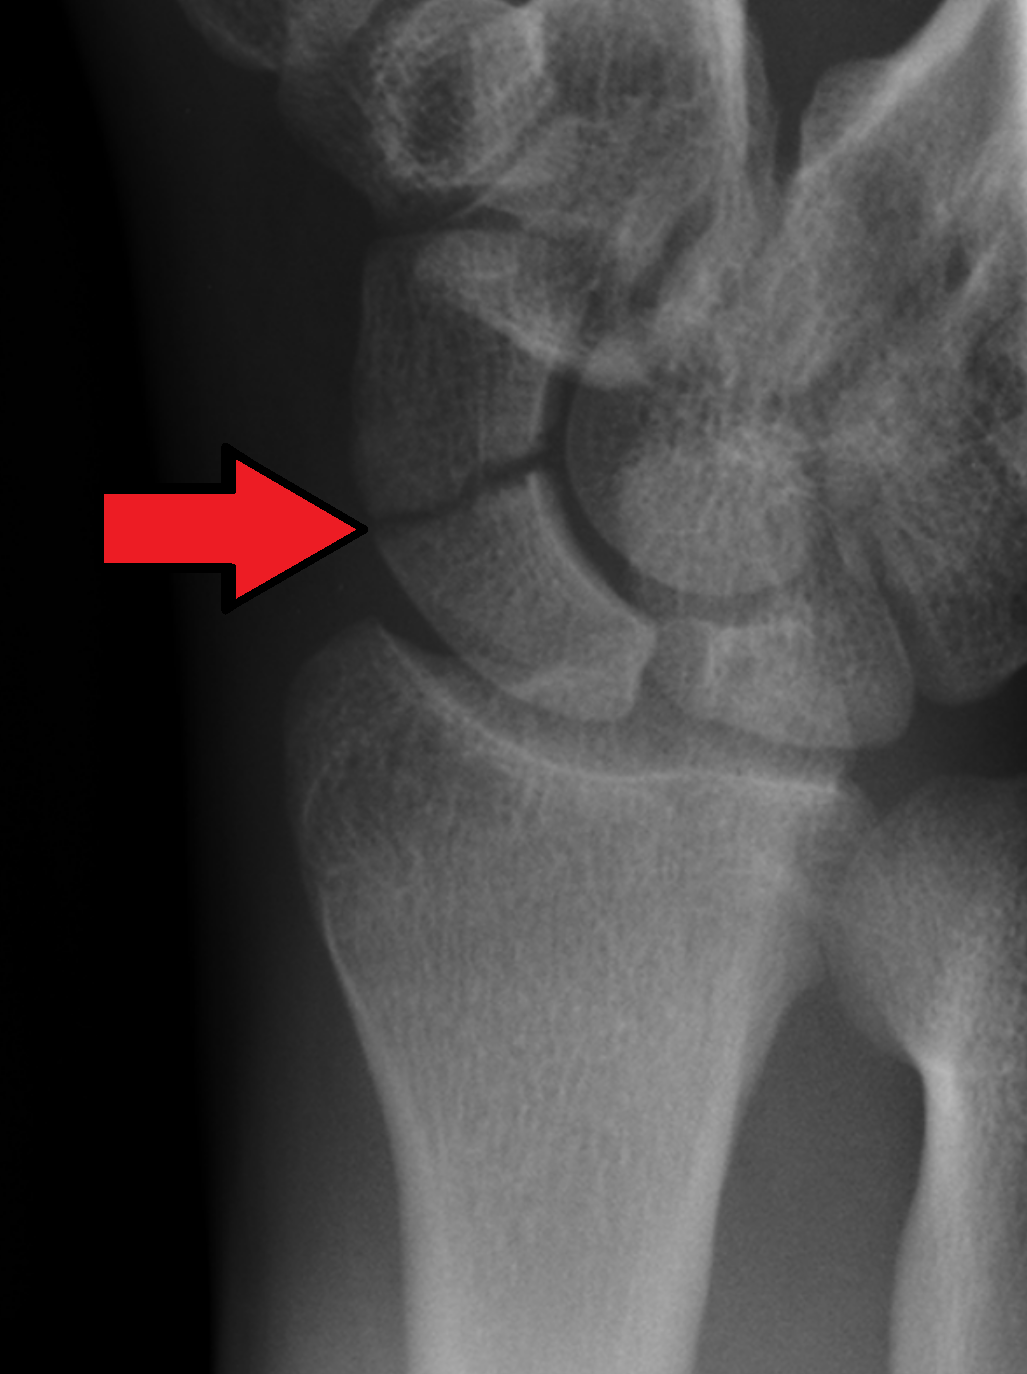

골절은 대게 Waist 라고 불리는 가운데 부분에서 진행되는 경우가 많으며(2), 10%는 근위부(1), 나머지 극소수(3)에서는 원위부에서 이러한 골절이 이러나게 됩니다.

주상골 골절의 가장 큰 골치아픈 점은 불유합이나 무혈성괴사 가 발생할 수 있다는 것입니다.

전방부 쪽으로는 : Superficial palmar br. of radial artery 가 20~30% 혈류를 공급하며

후방부 쪽으로는 Dorsal carpal br. of radial a. 가 70~80% 혈류를 공급합니다.

Waist 에서 Proximal에 가까이 골절될 수록 혈행 공급이 줄어들거나 차단이 될 수 있어, 지연유합이나, 불유합, 근위 골절편의 무혈성 괴사를 꼭 의심해보아야 합니다.